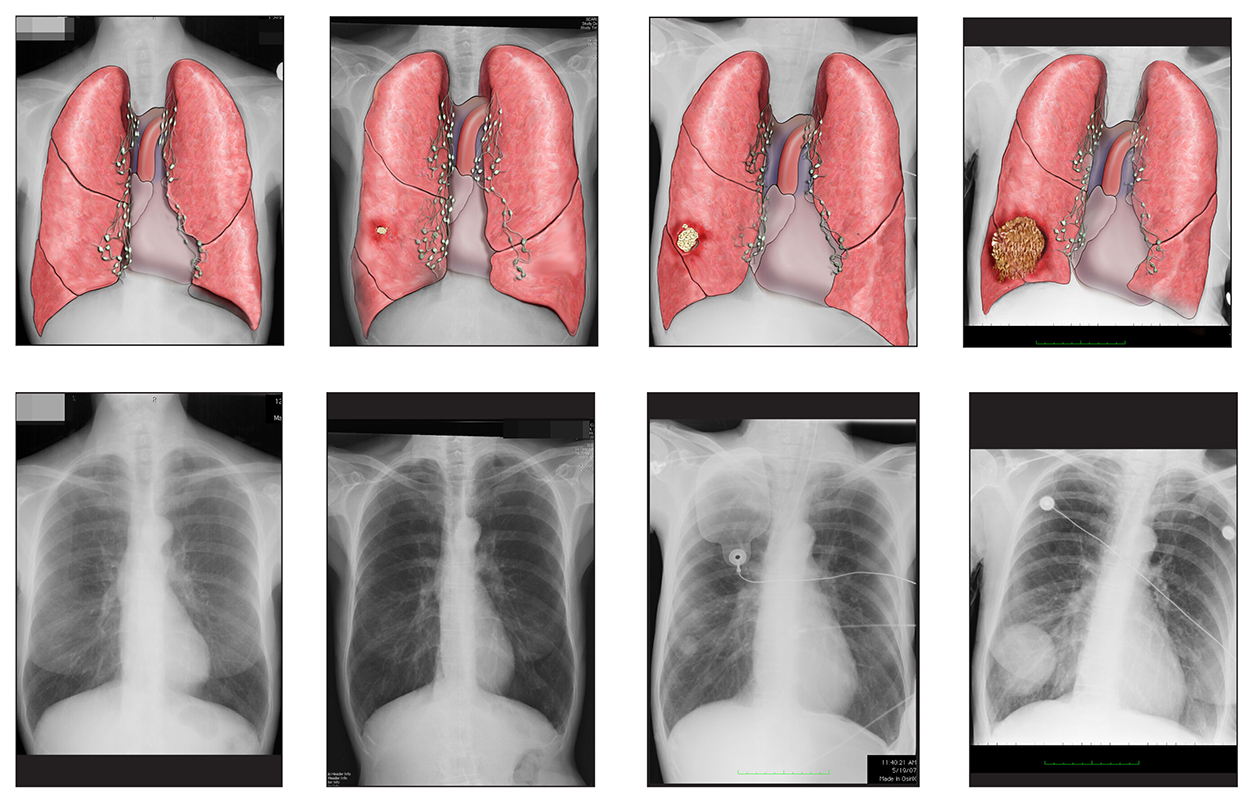

Lung Cancer Screening X Ray

Experience the clarity of Lung Cancer Screening X Ray with our curated collection of comprehensive galleries of images. featuring understated examples of photography, images, and pictures. designed to emphasize clarity and focus. Discover high-resolution Lung Cancer Screening X Ray images optimized for various applications. Suitable for various applications including web design, social media, personal projects, and digital content creation All Lung Cancer Screening X Ray images are available in high resolution with professional-grade quality, optimized for both digital and print applications, and include comprehensive metadata for easy organization and usage. Our Lung Cancer Screening X Ray gallery offers diverse visual resources to bring your ideas to life. Comprehensive tagging systems facilitate quick discovery of relevant Lung Cancer Screening X Ray content. Multiple resolution options ensure optimal performance across different platforms and applications. Time-saving browsing features help users locate ideal Lung Cancer Screening X Ray images quickly. The Lung Cancer Screening X Ray archive serves professionals, educators, and creatives across diverse industries. Instant download capabilities enable immediate access to chosen Lung Cancer Screening X Ray images. Whether for commercial projects or personal use, our Lung Cancer Screening X Ray collection delivers consistent excellence. Professional licensing options accommodate both commercial and educational usage requirements.